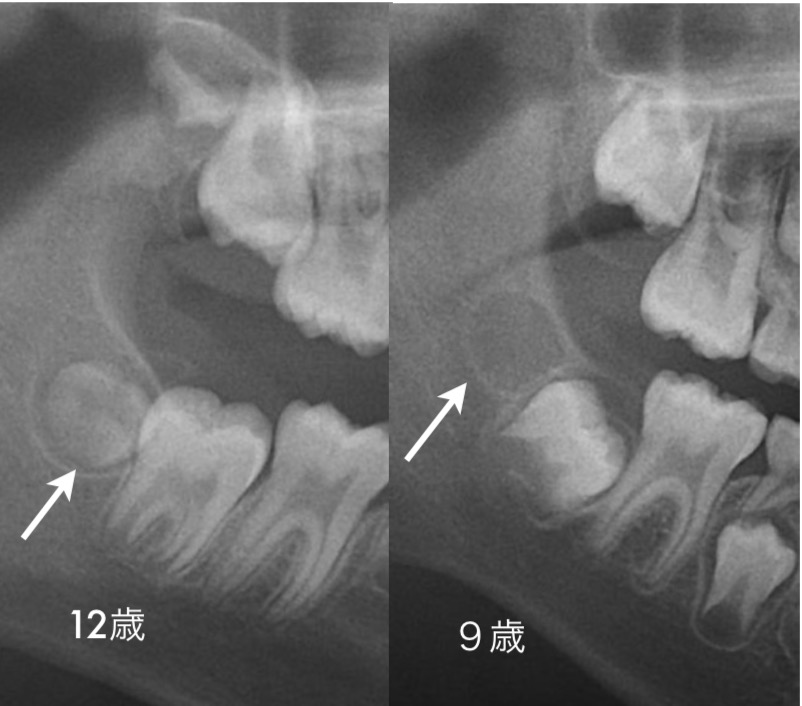

先日の外科矯正のセミナーで痛くない親知らずの

矢印のところにすでにエナメル質が半分ほど完成し

ています。この時点で抜くとまだマシですが、やは

り切開して抜歯になります。それなりに痛いと思い

ます。右の写真は9歳。矢印のところにある黒い穴の

ようなモノが将来の親しらずです。まだ石灰化がは

じまっていないので、簡単に取ることができます。

切開して、この黒いゼリー状の物体を取り出せばお

わり。残念ながら症状が全くないので、まさに「未病」です。残念ながら、「未病」は保険治療でき

ません。あしからずご了承ください。